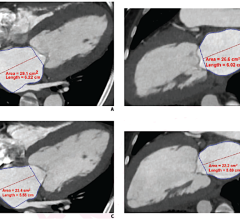

One of the clinical applications that comes with the software is VOXAR 3D CARDIAMETRIX for analysis of CT cardiac images. CARDIAMETRIX provides reading capability for cardiac 4-D analysis, coronary vessel analysis, left ventricular analysis and calcium scoring.